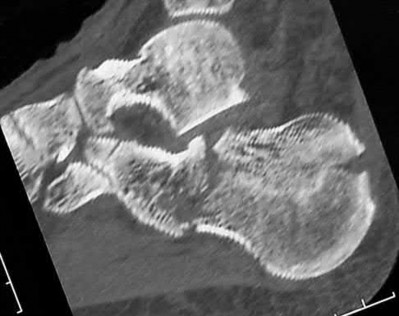

A 25-year-old female is involved in a motor vehicle collision. She presents with the isolated injury seen in Figures A through D. Her leg is swollen but her skin is intact. She has no clinical signs of compartment syndrome. Which of the following treatment options will allow for maintenance of fracture alignment and minimize the risk of soft tissue complications?

The patient presents with a closed distal third metaphyseal-diaphyseal distal tibia fracture with simple intra-articular extension. Immediate intramedullary nailing along with percutaneous fixation of the articular component provides appropriate restoration of length, rotation and alignment and minimizes the risk of wound complication.

Displaced distal third tibia fractures may be associated with simple intraarticular extension. Operative treatment of intra-articular distal tibia fractures has historically been performed with open reduction and internal fixation. Early open reduction and plate fixation of pilon fractures has been associated with high rates of infection and wound complication. In select patterns with simple articular extension, percutaneous screw fixation and medullary nailing may provide appropriate reduction with minimal soft-tissue risk.

Figures A and B demonstrate a distal third tibial shaft fracture with simple intra-articular extension. The axial and coronal CT cuts in Figures C and D further clarify the articular injury. Illustrations A and B demonstrate a comminuted distal third tibial fracture with simple intra-articular extension. Illustrations C and D are fluoroscopic images of the same injury after intramedullary nailing and percutaneous fixation of the articular component.